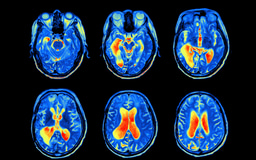

Reducing Excessive Microglia Activation to Reduce Neurodegeneration

Research Poster from 6-week project detailing possible treatments for Alzheimer's Disease and methods for epigenetic modification to modulate neurodegeneration.